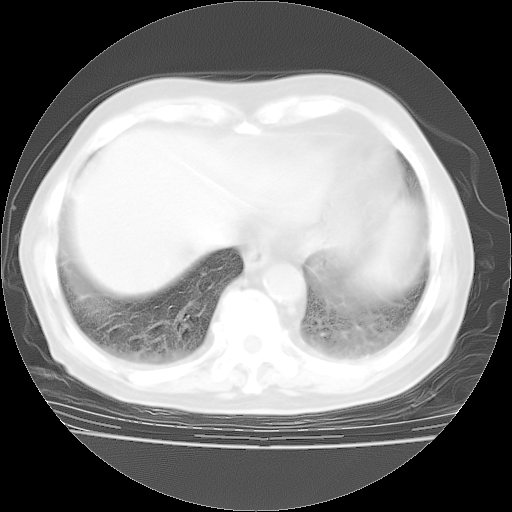

4月28日肺部CT——再次出现类似去年5月9日——透光度降低,“间质性”改变。

4月28日肺部CT——再次出现类似去年5月9日——磨玻璃样、间有“粟粒样”改变。